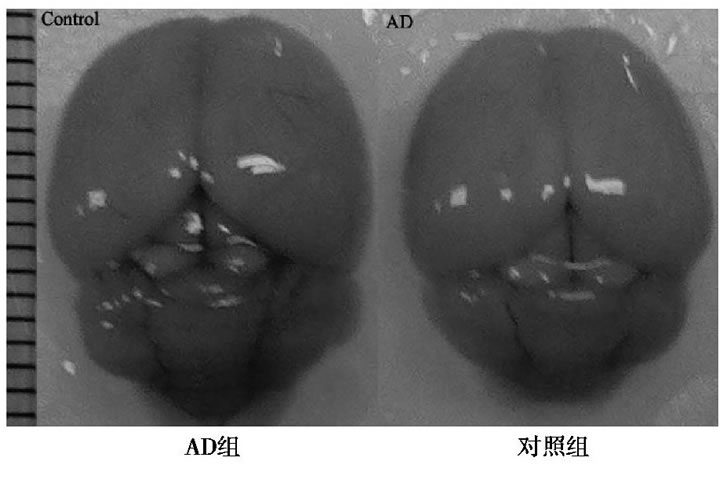

與對(duì)照組比較, AD小鼠完整腦組織表面泛白、無血色, 血管明顯減少, 表明D-半乳糖聯(lián)合三氯化鋁已經(jīng)對(duì)小鼠的腦組織形成退行性損傷。見圖1。

圖1 AD組和對(duì)照組小鼠全腦圖